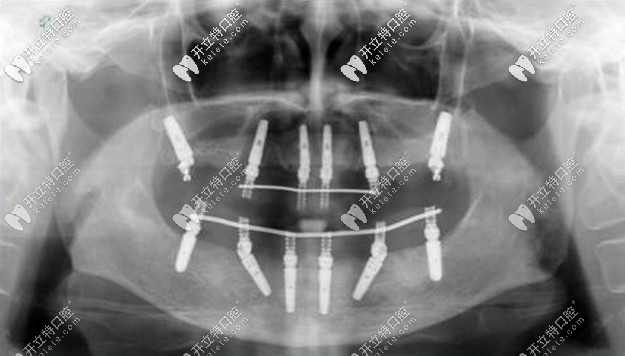

老人種牙All-on-4全口種植牙——價格在16萬-25萬之間,上下牙各四顆種植釘,利用8個植體就可以變好全口牙齒的咀嚼功能,種植顆數(shù)少,相比柵欄式種植更加便宜。

allon4全口種植牙